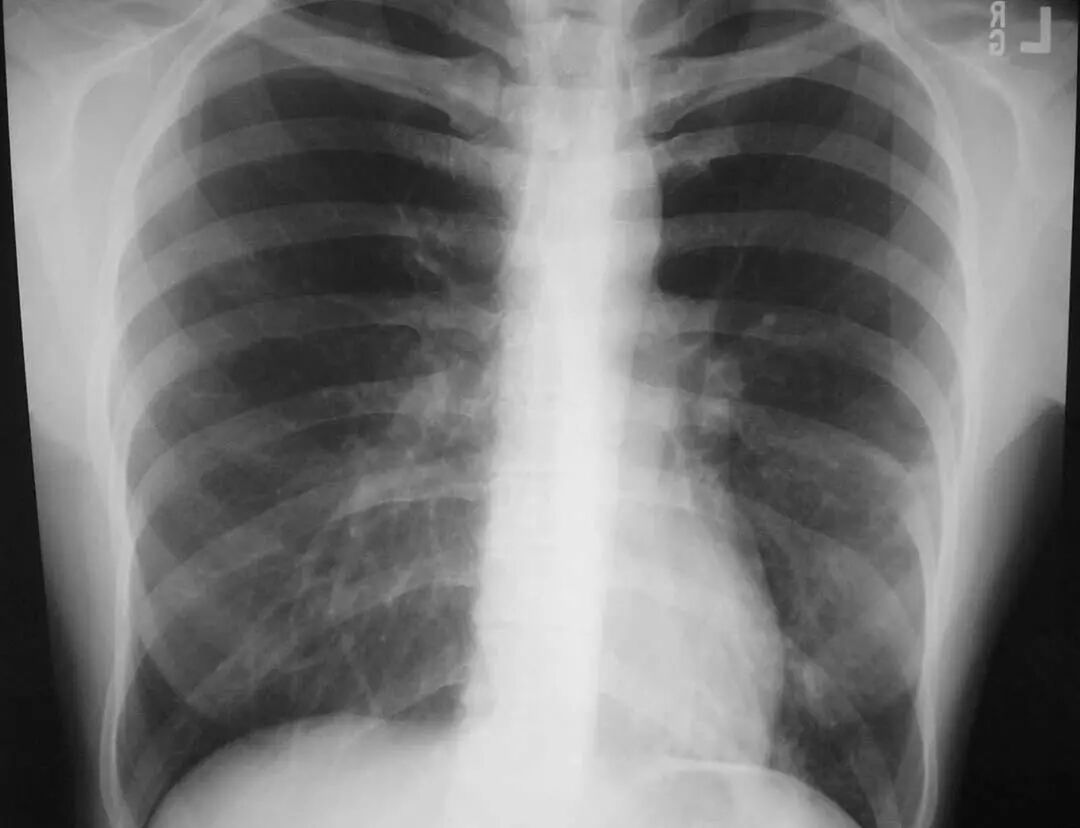

图1.1 细菌性肺炎。右上叶肺炎患者的放射影像。胸廓前后径增大,提示有慢性阻塞性肺疾病(COPD)。